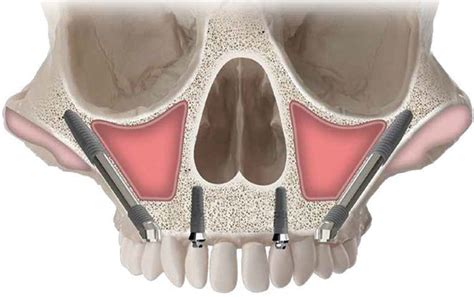

Chirurgia Oro-Mascellare per riabilitazioni protesiche post oncologiche

I pazienti che per motivi oncologici o per esito di osteonecrosi per uso di farmaci della categoria bifosfonati (in uso nelle gravi forme di osteoporosi o nel trattamento coadiuvante delle metastasi ossee)hanno subito gravi demolizioni dei mascellari e conseguente perdita della funzionalità masticatoria necessitano di ricostruzione e rifunzionalizzazione dell'apparato masticatorio con ricostruzione dell'osso mandibolare o del mascellare superiore attraverso innesti di osso , di lembi mucosi e/o muscolari di vicinanza ed a volte di implantologia preprotesica con impianti zigomatici , pterigoidei o convenzionali , tutto cio'con il fine di ripristinare una corretta funzione ma anche una auspicabile vita di relazione.